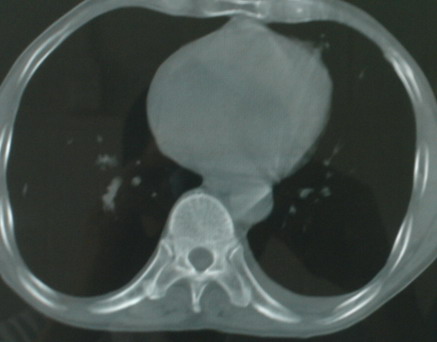

以下是引用医影拾贝在2008-6-3 18:48:00的发言:[br]双上肺弥漫性小结节影,纵隔窗内钙化淋巴结影,考虑血播性tb可能性较大,不除外肺ca可能

以下是引用卜一在2008-6-3 19:33:00的发言:[br]双肺结节,以双上肺分布为多,期间搀杂片状致密影及索条致密影。考虑:继发性肺结核伴血型播散可能性大。不除外肺泡ca的可能!另:椎体退变!

以下是引用panyishengct在2008-6-3 21:09:00的发言:[br]双上肺弥漫性小结节影,纵隔窗内钙化淋巴结影,考虑矽肺或/和tb可能性较大,不除外肺ca可能。腰椎考虑退变。 [br][br]